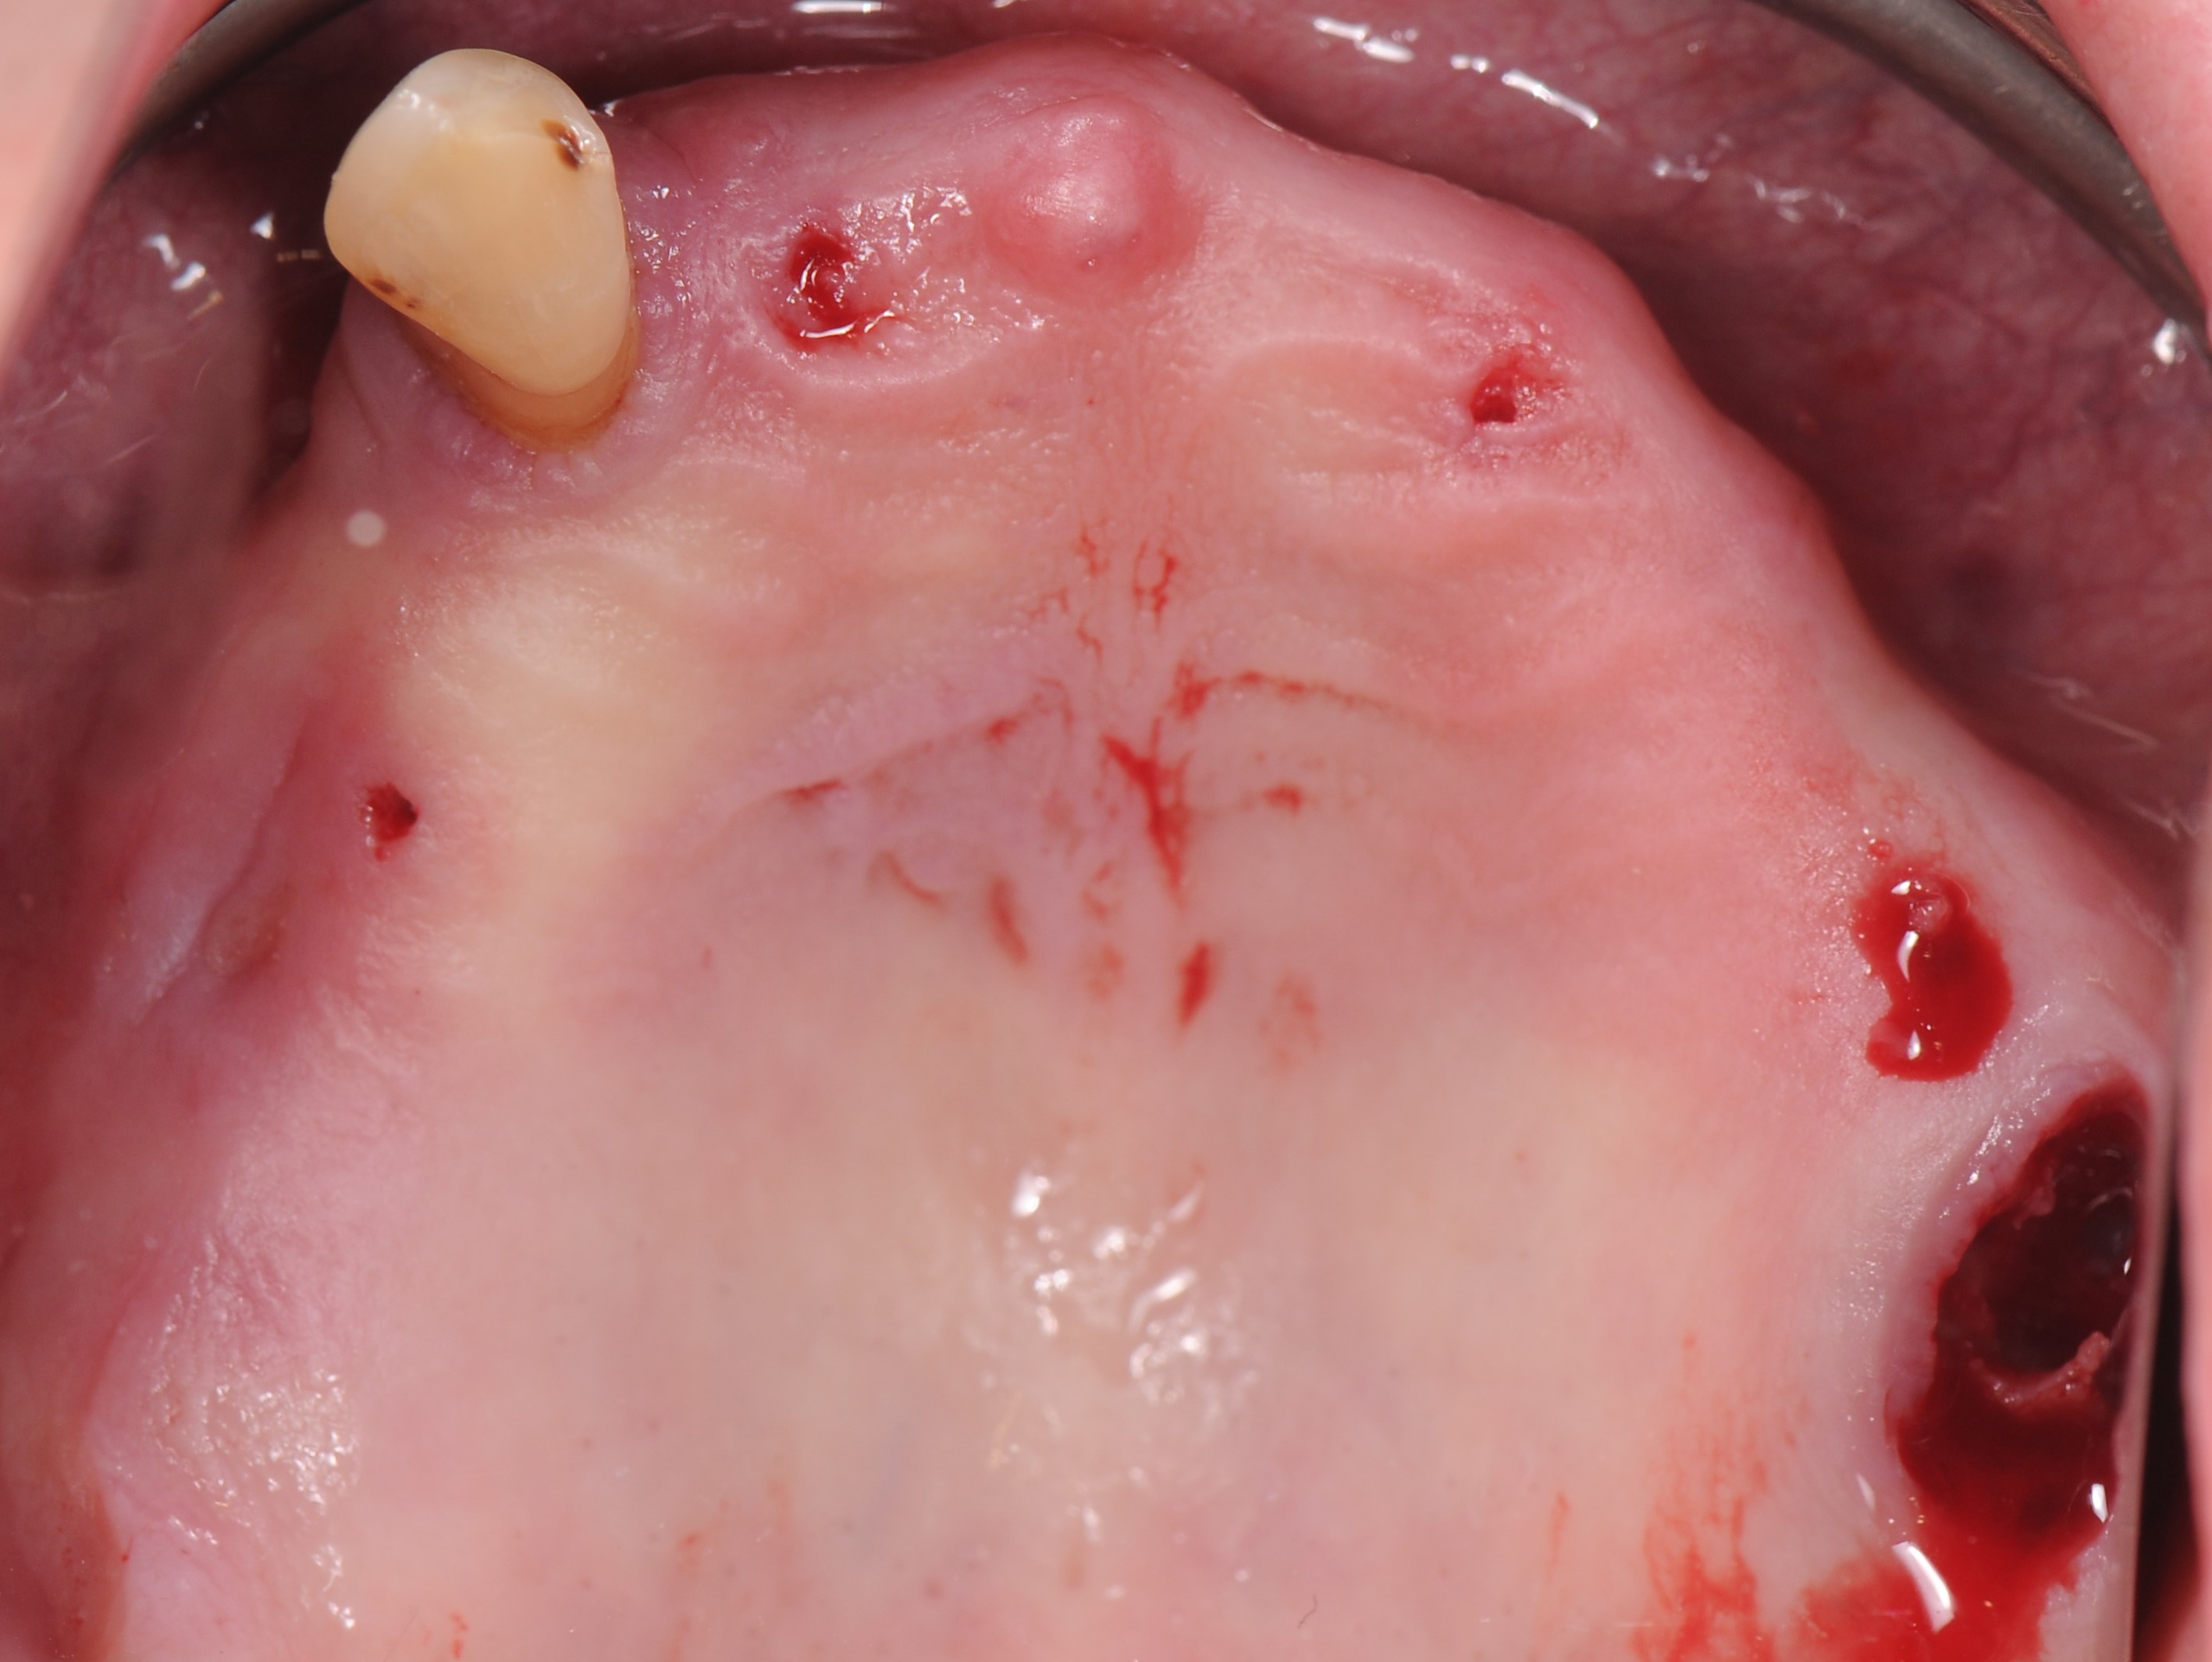

В полости рта наблюдаются пародонтальных патологии имеющихся зубов, зубоальвеолярное изменение в виде феномена Попова – Годона (рис 1,2,3.)

На панорамной рентгенограмме отмечаются: пневматизация верхнечелюстных синусов, значительная утрата пародонтальной поддержки зубов 2.7, 3.1, 4.1, 4.2, 4.5, 4.7, выраженная атрофия беззубых участков челюсти (рис 4).